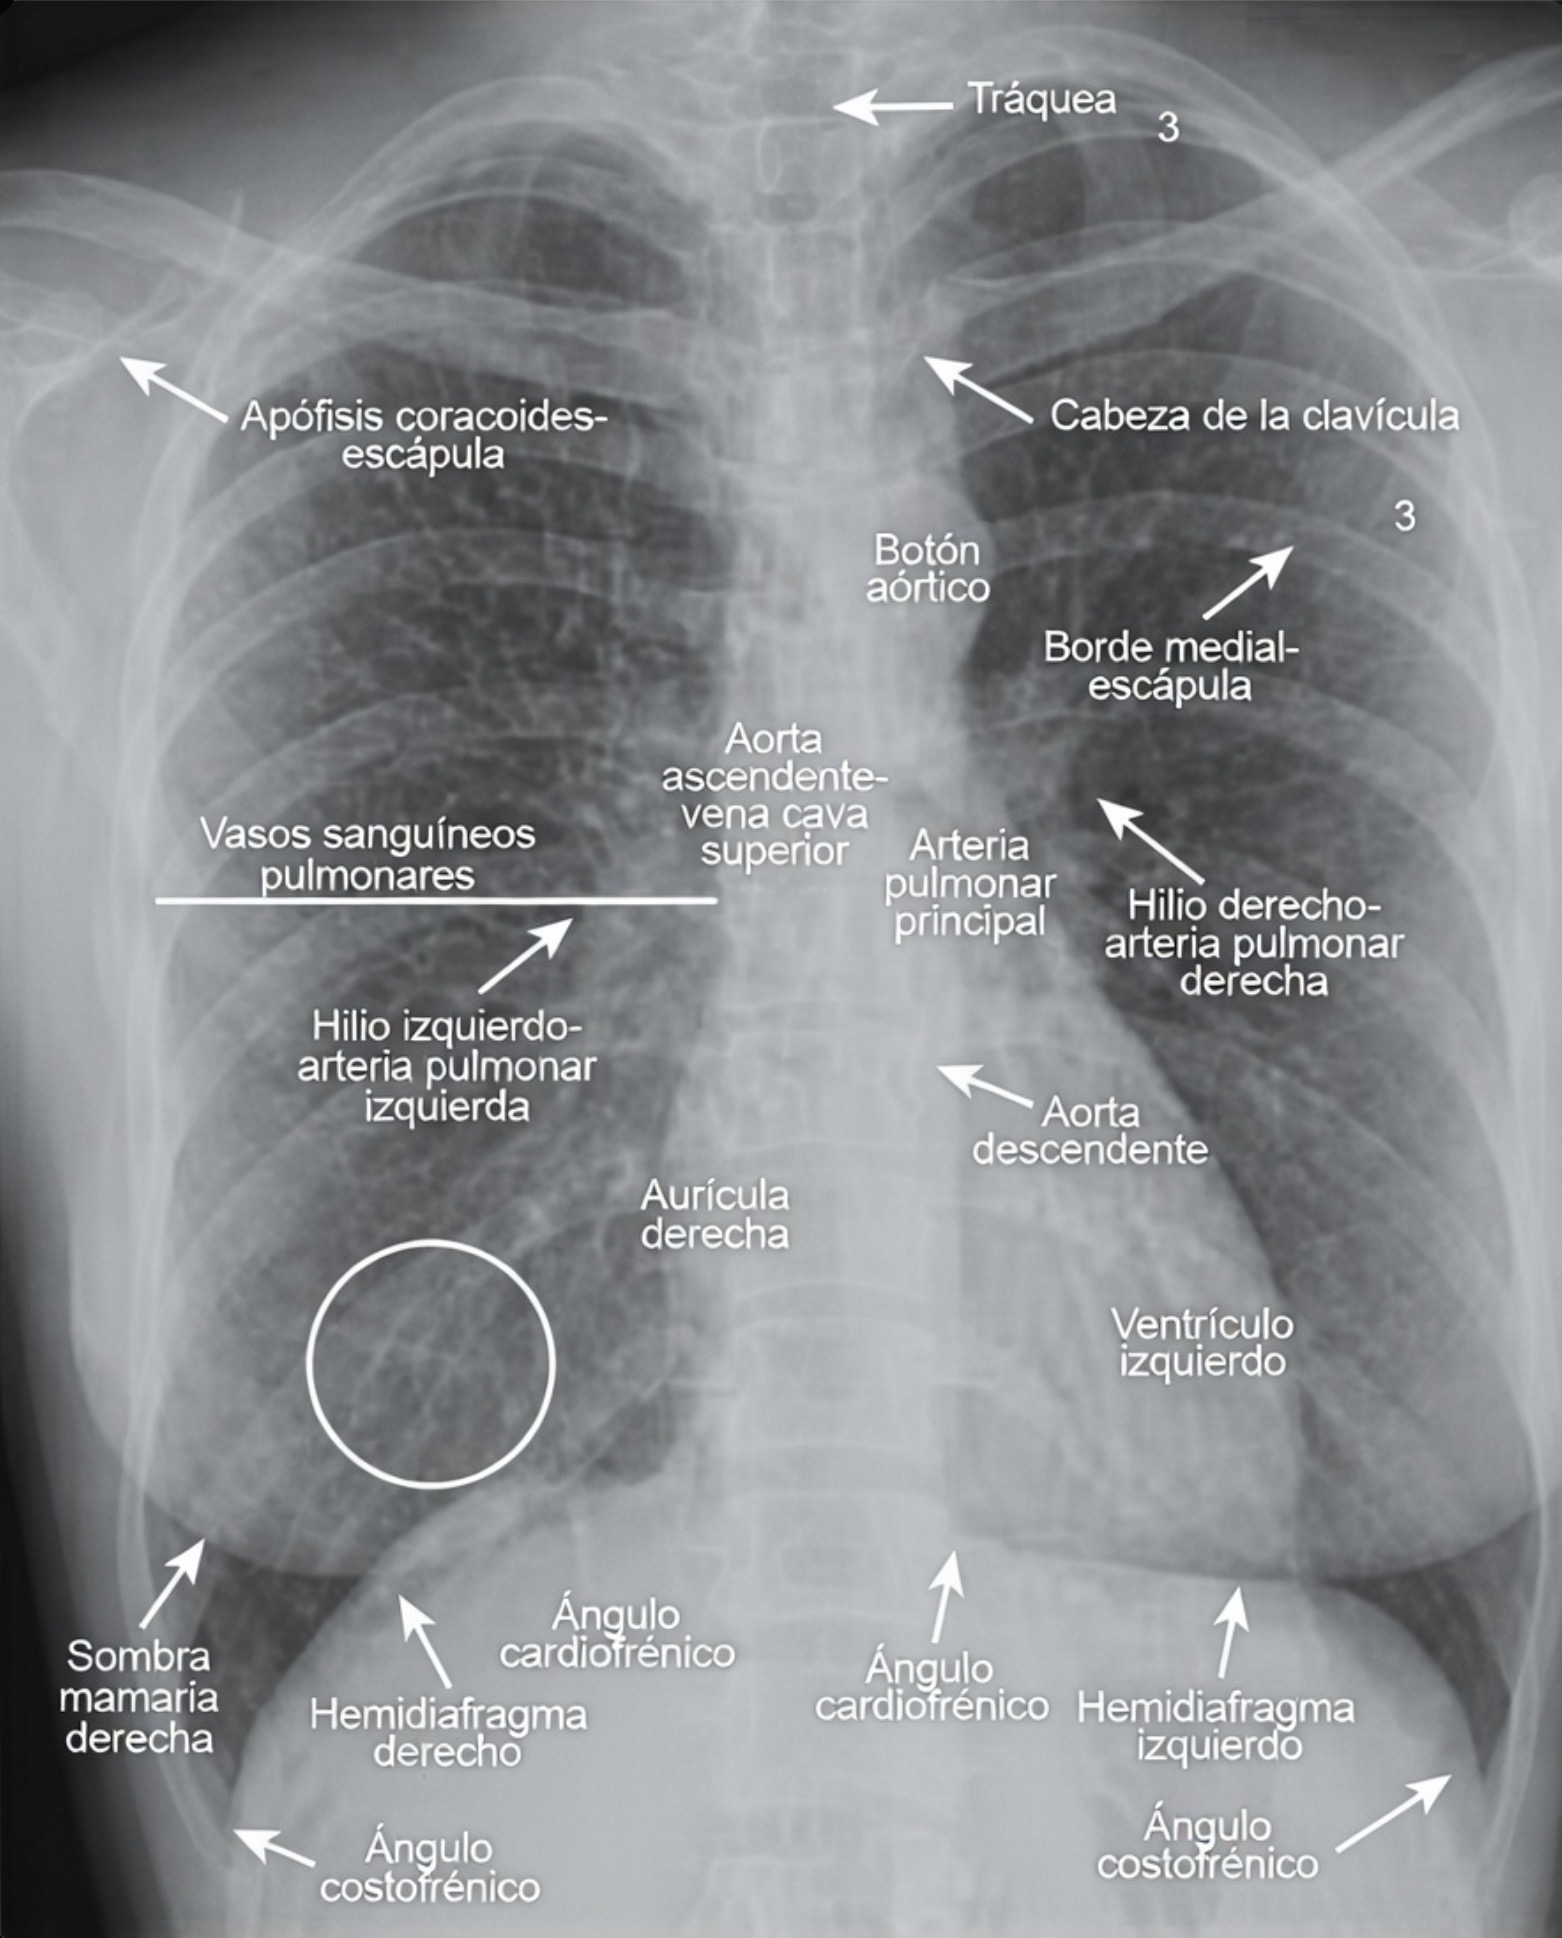

Identificación de la anatomía pulmonar normal en la radiografía frontal de tórax

El reconocimiento preciso de la anatomía pulmonar normal en la radiografía frontal de tórax constituye el fundamento indispensable para toda interpretación radiológica rigurosa. Antes de identificar la enfermedad, el observador debe haber interiorizado profundamente la morfología, la disposición espacial y el comportamiento radiográfico de las estructuras normales. Solo a partir de este conocimiento es posible distinguir variaciones fisiológicas de verdaderas alteraciones patológicas.

La radiografía frontal de tórax es una representación bidimensional de estructuras tridimensionales superpuestas. Esta característica implica que múltiples tejidos de diferente densidad se proyectan en un mismo plano, generando una imagen compleja cuya correcta interpretación exige comprender tanto la anatomía como los principios físicos de la formación de la imagen radiográfica. La capacidad para diferenciar lo normal de lo anómalo no depende únicamente de la agudeza visual, sino del conocimiento anatómico previamente consolidado.

En una radiografía frontal correctamente realizada, la columna vertebral torácica debe visualizarse tenuemente a través de la silueta cardiaca, lo cual indica una penetración radiográfica adecuada. Los ángulos costofrénicos laterales derecho e izquierdo deben observarse agudos y bien definidos, reflejando la ausencia de líquido o engrosamiento pleural significativo.

Un rasgo anatómico importante es que el hilio pulmonar izquierdo suele situarse ligeramente más alto que el derecho. Esta diferencia obedece a la disposición anatómica de las arterias pulmonares y a la relación con el corazón y el arco aórtico. Reconocer esta asimetría como una característica normal evita interpretaciones erróneas.

Asimismo, en el hemitórax derecho suele identificarse la cisura menor u horizontal, que separa el lóbulo superior del lóbulo medio del pulmón derecho. En el pulmón izquierdo no existe cisura menor, ya que este órgano está dividido únicamente en dos lóbulos por la cisura mayor u oblicua. La visualización de estas cisuras es un fenómeno óptico derivado del pliegue de la pleura visceral.

La identificación de las costillas también requiere precisión. Las porciones posteriores de las costillas se observan más horizontales y densas, mientras que las porciones anteriores adoptan una orientación descendente hacia el esternón. Diferenciar ambas evita errores al contar espacios intercostales o valorar el grado de inspiración.

La mayor parte de las opacidades lineales visibles dentro de los campos pulmonares corresponde a vasos sanguíneos. Estas estructuras se originan en los hilios y se distribuyen hacia la periferia siguiendo un patrón ramificado. A medida que se alejan del centro, disminuyen progresivamente de calibre.

En condiciones normales, no es posible distinguir con exactitud las arterias pulmonares de las venas pulmonares en la radiografía convencional, debido a que ambas presentan densidades y trayectorias similares. Sin embargo, el patrón general de arborización y adelgazamiento progresivo constituye un elemento esencial para reconocer la normalidad.